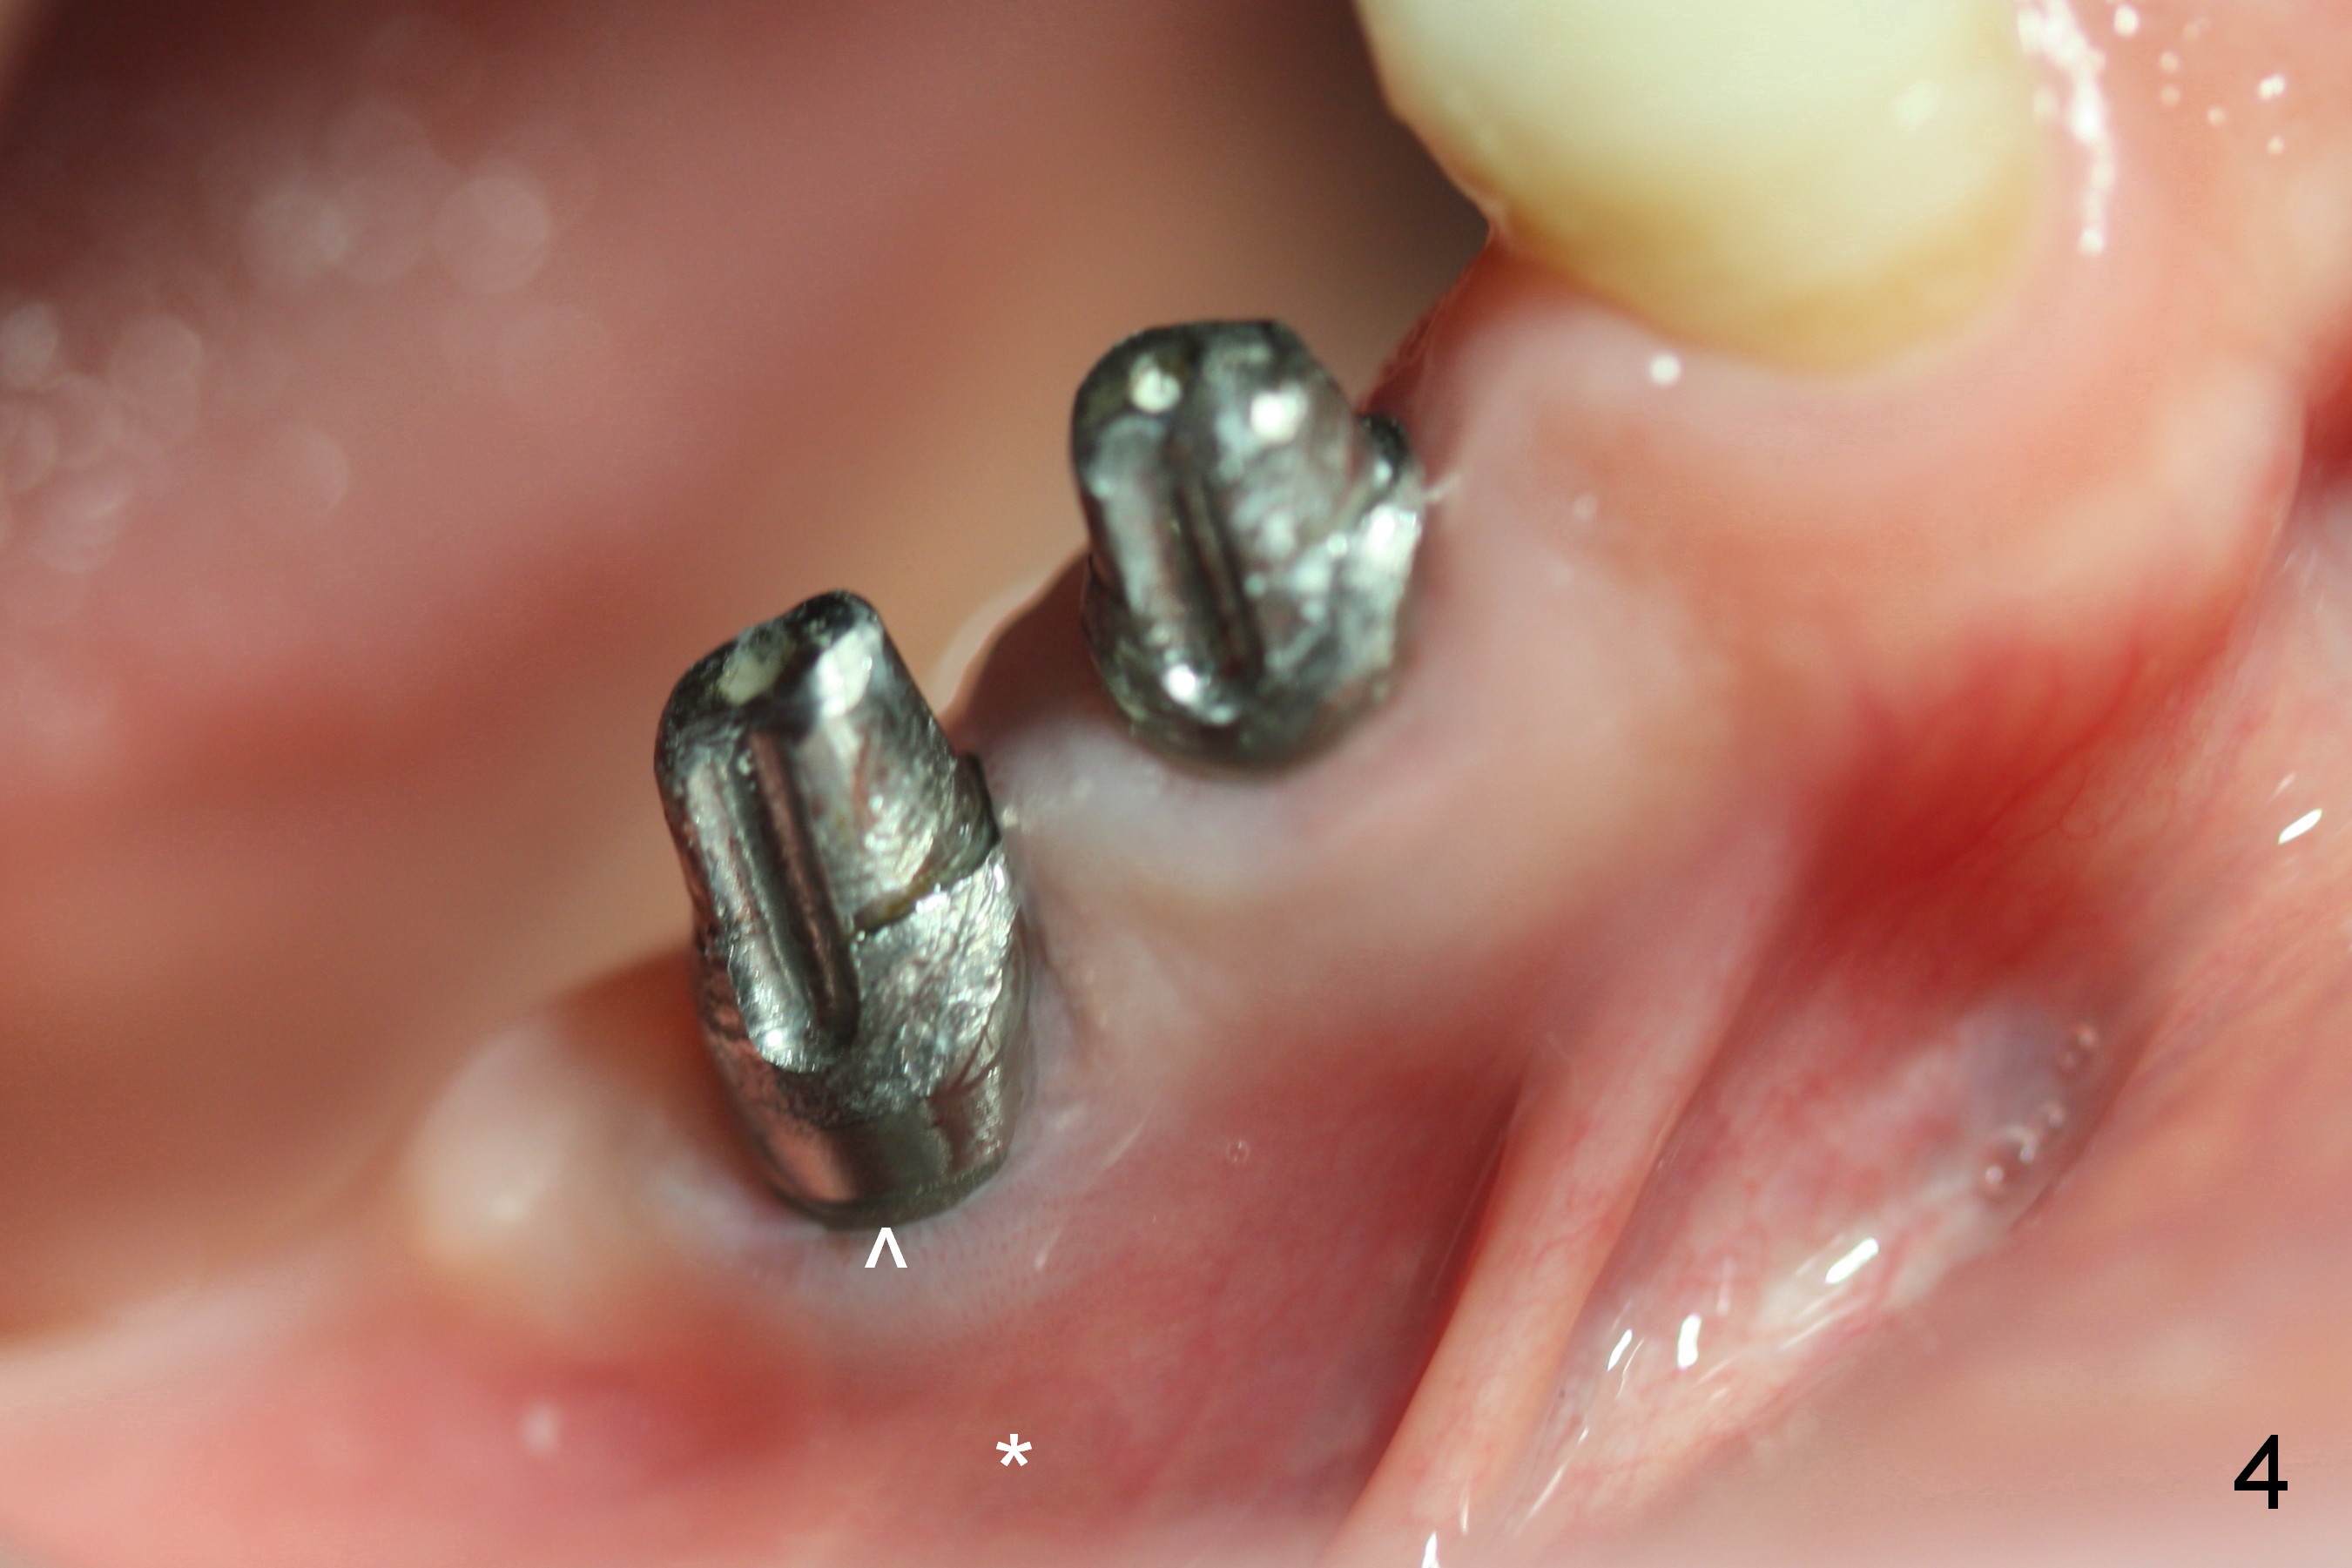

Fig.1 shows preop condition, whereas Fig.2 immediately post placement. In fact there is a space lingual to the implant of #29 (*). At that moment, the buccal margin is within normal limit (arrowheads). Ideally, the malpositioning can be corrected immediately. The implant should have been removed, repositioned and placed at the right position and trajectory. It is possible that attention was being paid to the depth of the osteotomies, because of proximity to the Mental Loop.

Four months and a half, the buccal margin has to be extended (Fig.3 ^). A month later, gingival recession becomes more obvious (Fig.4 ^ with exposure of the rough surface of the implant). Occlusal view demonstrates the buccal position of the implant and abutment at #29 (Fig.5). CBCT will be taken to confirm the malpositioning. If it is confirmed, the abutment and implant will be removed and un-torqued. The lingual bone will be removed; osteotomy will be also extended apically cautiously. The same or longer implant will be placed immediately. Probably two 1 piece implants will be placed at the same time at the site of #30, since the ridge is narrow.